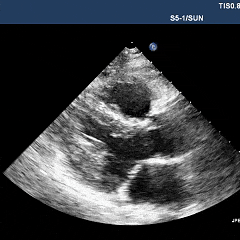

超声心动图显示,在左心室中侧壁邻近前乳头肌处,有一大小约27.5×16.5mm的中等回声团块,与邻近结构分界不清(图1A、1B,动图1、2)。通过胸骨旁长轴、改良胸骨旁短轴及心尖四腔心切面进行彩色多普勒检查,未探测到明确的瘤内血流信号,考虑血流信号的缺失很可能源于声学局限性。

动图1、2